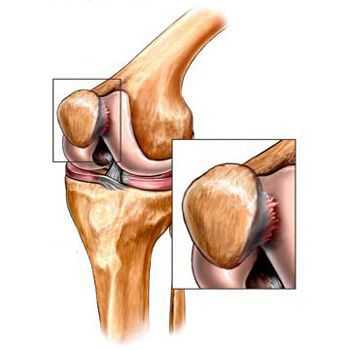

- пателлофеморальный артроз (поражение надколеннико-бедренного сочленения );

Помимо внутреннего или наружного отдела колена артроз может поражать и поверхности между надколенником и межмыщелковой бороздой бедренной кости. Такой вариант называется пателло-феморальный артроз. [16]

Его причиной, как правило, становится подвывих, перелом или латерализация надколенника.